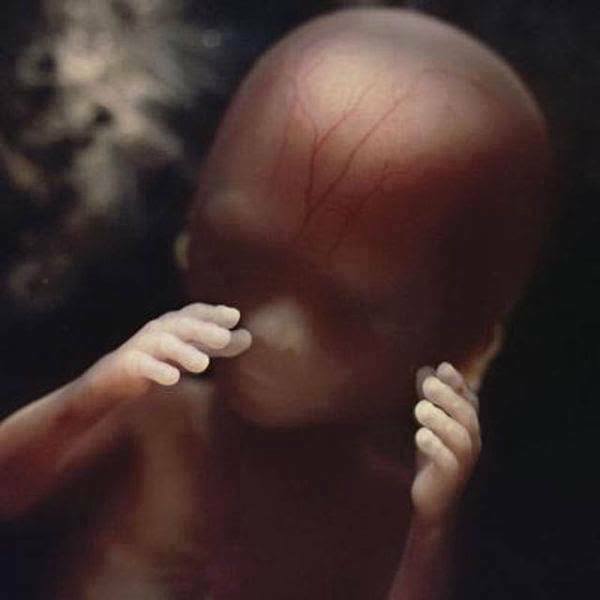

11. 懷孕5周時,胚胎大概只有9毫米大,但臉部已經逐漸成形,可以大致看出來眼睛、鼻子和嘴巴的形狀了。

12. 懷孕40天時,外層的胚胎細胞和子宮表層連結,形成了胎盤,而胎盤能夠透過母體的血液獲取營養與氧氣,並排出廢物。